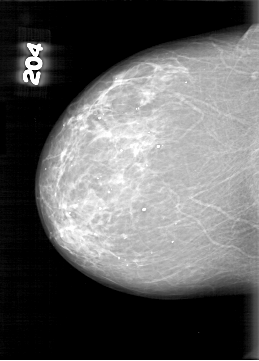

D_4098_1.RIGHT_CC

RIGHT_CC LINES 6481 PIXELS_PER_LINE 4651 BITS_PER_PIXEL 12 RESOLUTION 43.5 NON_OVERLAY